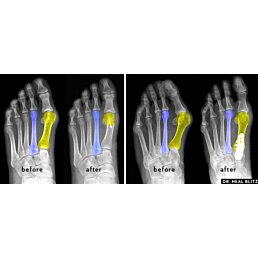

Hallux valgus (vbočený palec) je jednou z najčastejších deformácií chodidla, ktorá spôsobuje vychýlenie palca smerom k ostatným prstom. Tento problém vedie nielen k estetickým nepríjemnostiam, ale aj k bolestiam, podráždeniu kože a vzniku otlakov.